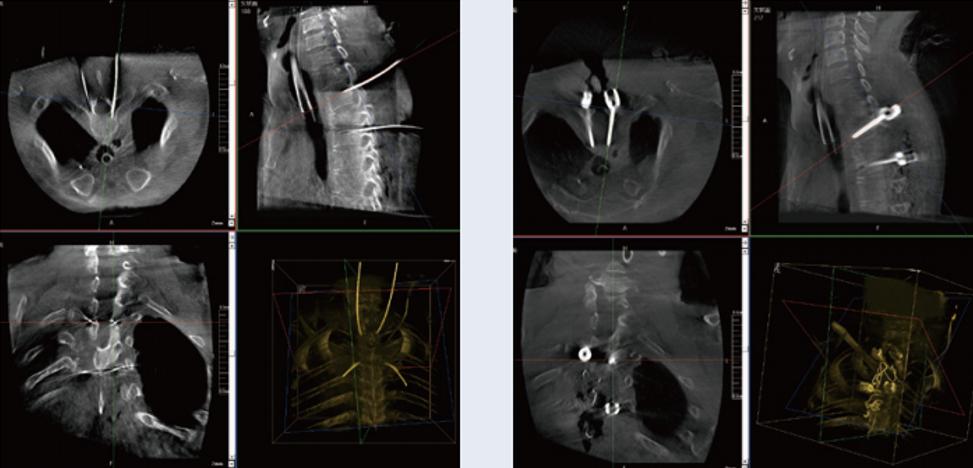

螺釘規劃后的圖像

術中三維C形臂影像在脊柱導航機器人系統中的應用

植入螺釘后的圖像

術中三維C形臂與脊柱導航機器人配合應用,實現準確定位,確保了手術安全、高效完成。術后二維、三維影像顯示手術效果良好,達到預期目的。